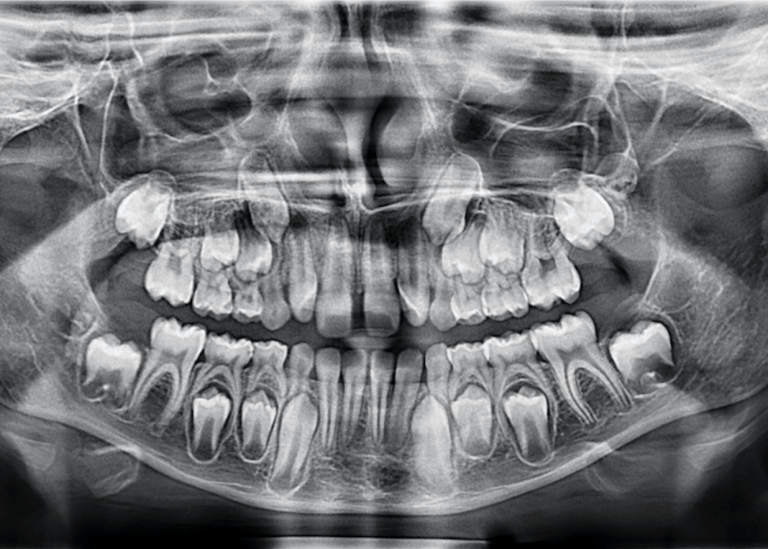

- увидеть зачатки постоянных зубов у детей;

- определить строки смены молочных зубов на постоянные;

- Детская стоматология – определения положения зачатков постоянных зубов.

- с помощью него доктор может увидеть зачатки постоянных зубов у малышей и обнаружить возможные патологии их развития;